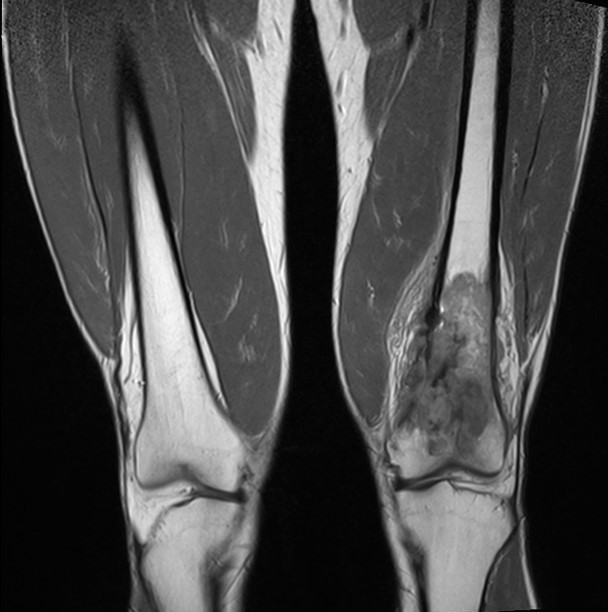

2. Բժշկական տարբեր կենտրոններում հետազոտվելուց հետո՝ 17-ամյա պատանին դիմել է «Նաիրի» ԲԿ։ Համապատասխան հետազոտություններ անցնելուց հետո՝ բուժառուի մոտ հայտնաբերվել է ոլոքի օստեոսարկոմա (ոսկրային քաղցկեղ): Նախավիրահատական բուժում ՝ քիմիոթերապիա, ստանալուց հետո՝ «Նաիրի» ԲԿ ում կատարվել է օրգանապահպան վիրահատություն : Հեռացվել են ծնկահոդն ու ոլոքի վերին երորդականը: Առաջացած դեֆորմացիան շտկել է Եվրոպայից պատվիրված էդոպրոթեզով, որը հնարավորություն է տվել պահպանել վերջույթի գործառույթը՝ քայլել, վազել և այլն։ Հետվիրահատական շրջանում բուժառուն ստացել է քիմիոթերապիա։ Այժմ գտնվում է բժիշկների հսկողության ներքո։

Վիրահատությունից առաջ

Վիրահատությունից հետո